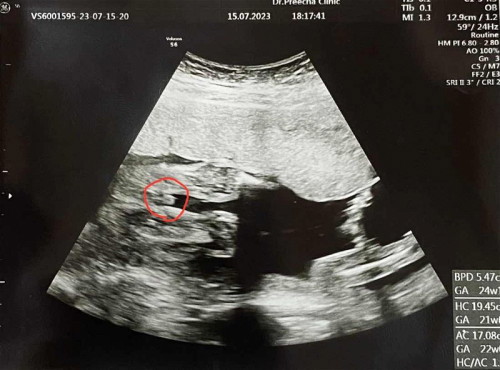

สอบถามรูปอัลตราซาวน์ค่ะ

คุณหมอบอกได้ผู้ชาย จู๋โผล่ คุณเเม่ว่าชัวร์มั้ยคะ ขอดูรูปอัลตราซาวน์เเม่ๆที่ได้ลูกผู้ชายหน่อยค่า

บ้านนี้หมอบอก เด็กผู้ชายค่ะ แต่คุณแม่ก็ไม่มั่นใจเหมือนกันค่ะ..ว่าชายชัวหรือเปล่า😂

ผลตรวจน้ำคร่ำก็บอกว่าเพศชายค่ะ สงสัยน้องกลัวแม่ไม่เชื่อ 🤣🤣